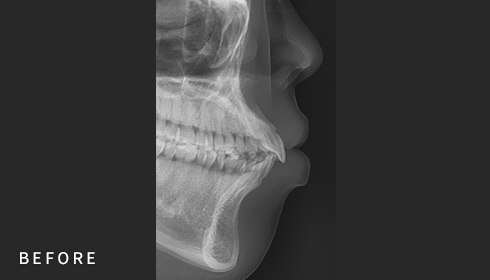

• Cephalometric X-ray 촬영

2~3초의 짧은 시간 안에

얼굴의 측면 엑스레이 촬영이 가능합니다.